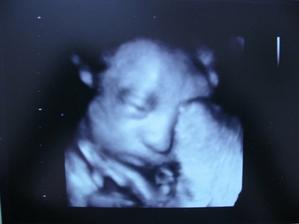

10.2.2009 další UZ - 21. týden. Všechno je v pořádku, miminko je tajemné, ale asi to bude holčička.

27.4.2009 - 32. týden a UZ. Je to opravdu holčička!!! I když nikdy není nic jisté 🙂